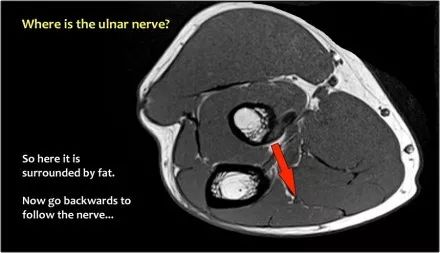

尺神经:在这里,我们看到了肘管内的尺神经。尺骨侧支带的后带形成隧道的底部,而支持带形成屋顶。

该患者有尺神经神经病变。肘管综合征是一种常见的周围神经病变。它产生于肘管内尺神经,其中该神经传递肘管支持带的下方的压缩。

肘管综合征的可能原因● 过度使用● 由于纤维组织中的先天性松弛,尺神经半脱位● 肱骨骨折伴游离体或愈伤组织形成● 由上髁或鹰嘴引起的关节炎● 存在肌肉异常● 软组织肿块:神经节,脂肪瘤,骨软骨瘤,继发于类风湿性关节炎的滑膜炎,感染(例如结核病)和出血。

当他们将尺神经带出隧道时,他们把它放在哪里,它可以是皮下,肌肉下或肌肉内。

因此,当我们回到图像时,您会发现很难找到神经。任何这些皮下结构都可以是转位神经。一种方法是远端跟随结构,直到你发现远端的尺神经位于由脂肪包围的前臂近端的正常位置。然后当你向近端跟随它时,你会发现这是皮下移位。

在这种情况下,有神经炎。神经增大。在T2W图像上有高信号。另一个标志是在矢状图像(箭头)上看到的束的不均匀扩大。